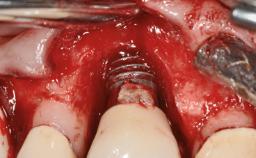

Repeated Acrylic Fractures on a Mandibular Fixed Full-arch Implant-supported Metal/Acrylic Prosthesis

A 77-year-old male patient was referred for the management of frequent and repeated acrylic fracture of his existing mandibular fixed full-arch implant-supported metal/acrylic prosthesis. He also complained about softtissue soreness and the lack of retention and stability of his maxillary removable partial metal/acrylic prosthesis. Both prostheses had been delivered two years previously as part of his full-mouth rehabilitation (caries, tooth wear, tooth fracture). His medical history revealed high blood pressure, controlled with the use of antihypertensive medication.